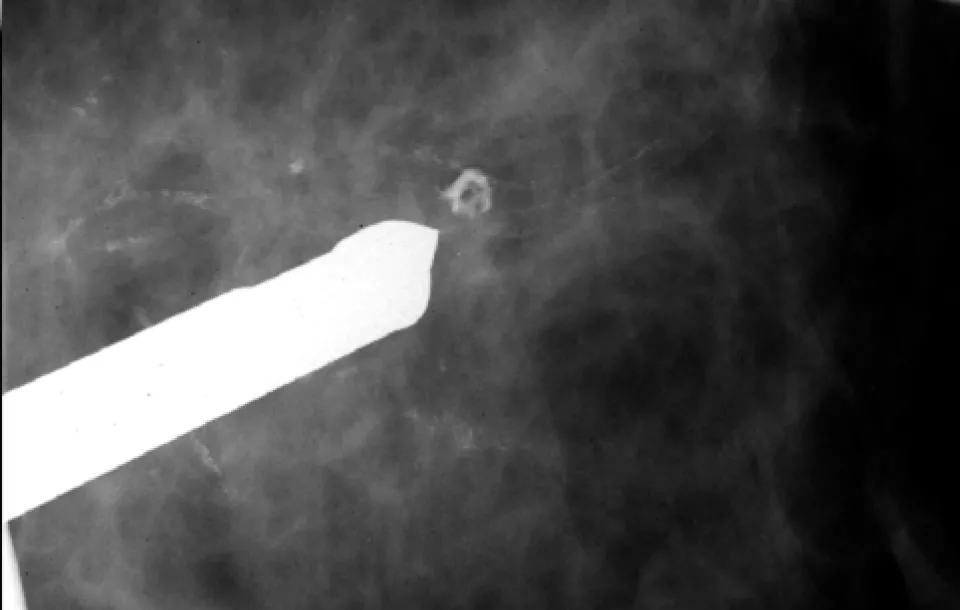

Stereotactic breast biopsy is used to obtain pathologic information from mammographic areas of suspicion. When a mass, microcalcifications, or area of abnormal tissue change exists, stereotactic breast biopsy offers a minimally invasive alternative to open surgical biopsy, often before a mass develops.